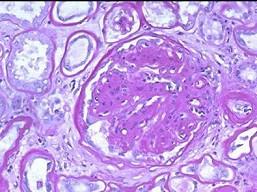

问题 下述两张病理图片示肾小球毛细血管袢呈结节样的粉红色玻璃样物质(K-W结节)。其诊断为 ( )

选项 A、硬化性肾炎 B、以上均不是 C、糖尿病性结节性肾小球硬化(Kimme1stie1-Wi1son病) D、局灶性肾炎 E、局灶节段性肾小球硬化

答案 C